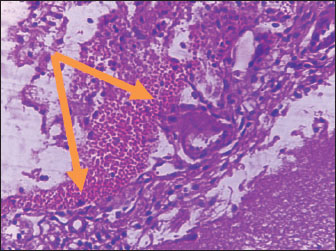

Brain of control group appeared normal structure of tissue with manifestation of Purkenji cells (Fig. 1), whereas sodium benzoate administration at low dose (200 mg/kg) occurred several histological lesions as hypertrophy of neurons (Fig. 2), pair nuclei arranged encompassed with clear space (Fig. 3), bleeding with degeneration of nerve cells (Figs. 4 and 5), respectively. In addition, lesions such as vacuolation, congestion, and accumulation of inflammatory cells were also evident (Figs. 6 and 7). However, severe histopathological lesions were observed following high-dose of sodium benzoate exposure, such as degeneration of neurons stained in dark blue (Fig. 8), prominent vascular duct with inflammation (Fig. 9), vacuolation, edema, and clear congestion as seen in Figures 1012, respectively.

Fig. 4. Points to the brain of sodium benzoate group (200 mg/kg): heavy hemorrhage (H&E) (100×).

Fig. 5. Points to the brain of sodium benzoate group (200 mg/kg): degeneration of neurons which stained in dark blue (H&E) (100×).

The histopathological lesions observed in the brain can be associated with two doses of sodium benzoate that cause defects in brain architecture. This agrees with the findings of Al-Ameen et al. (2022), who pointed to brain damage in the cortex, such as vacuolation, satellitosis, edema, and focal gliosis. The same study also described mild to severe changes according to the sodium benzoate ingestion dose. Similarly, a previous study by Mohammed and Al-Gnami (2022) referred to the passive histological effects of sodium benzoate in many tissues, causing vacuolation, degeneration, and infiltration of inflammatory cells. Furthermore, histopathological lesions may be due to DNA damage of neurons by sodium benzoate exposure. This is similar to the findings of Mohiuddin et al. (2022), who showed DNA fragments of rats treated with a high dose (120 mg/kg) of sodium benzoate.